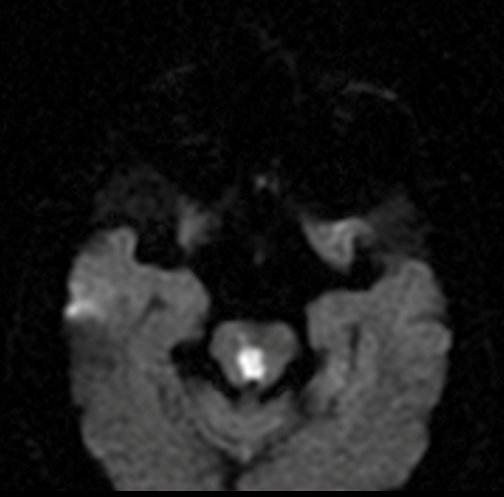

TAC de cráneo simple sin lesiones agudas, RM cerebral con imagen hiperintensa en difusión, hipointensa en ADC e hiperintensa en FLAIR a nivel de tegmento mesencefálico medial (ver imagen 2), compatible con infarto mesencefalico en etapa subaguda, no candidata a trombolisis, se realizaron estudios de factores de riesgo cardiovascular sin hallazgos significativos, se dio egreso con prevencion secundaria.

Imagen 2. RM cerebral en secuencia difusión, ADC y FLAIR